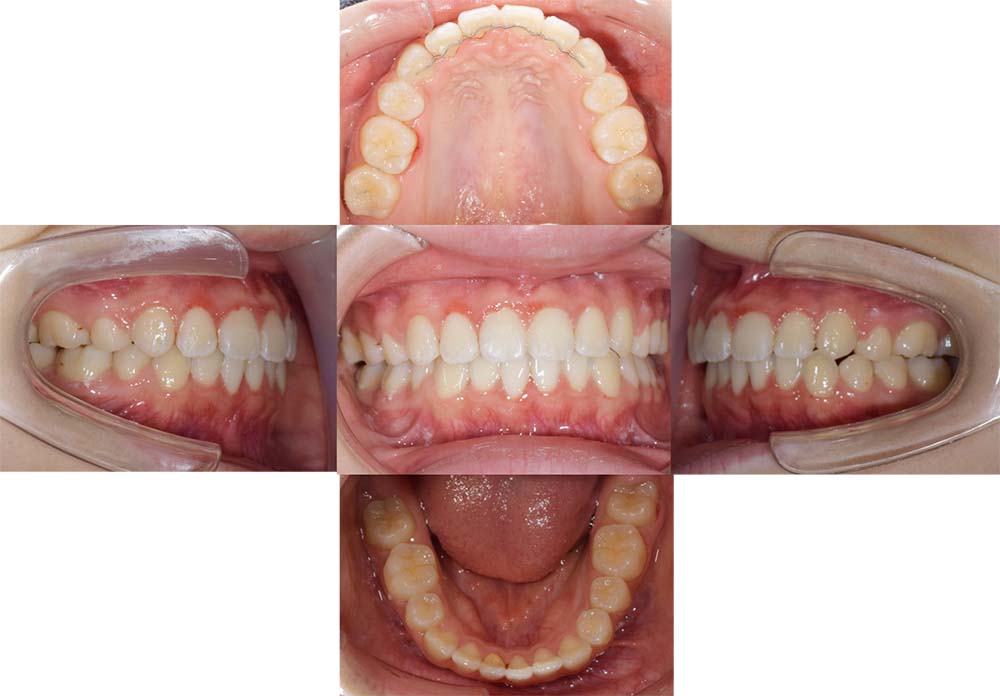

症例03

| 主訴 | 歯並びがガタガタしている。 |

| 診断名あるいは主な症状 | 過蓋咬合、叢生 |

| 年齢/性別 | 26歳・女性 |

| 矯正ステージ | 大人の矯正治療 |

| 治療方法 |

ワイヤー矯正 歯科矯正用アンカースクリュー(3本) |

| 抜歯部位/抜歯有無 | 抜歯 |

| 治療内容 | 上下顎の奥歯を後方に移動後、ガタガタの改善と上下顎前歯を後退させた。 |

| 費用 |

90万円程度(2025.10時点の料金となります。) ※矯正基本料金、アンカースクリュー、審美ブラケットを含む |

| 治療期間 | 2年8ヶ月 |

| 主なリスク・副作用 | 痛み、歯根吸収、歯肉退縮、虫歯、後戻り |